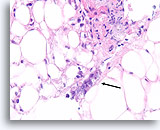

Lobulair carcinoom, Borst FNA, celblok.

Lobulaire carcinoomcellen lijken in het stromaweefsel te zijn ingebed, zodat de indruk wordt gewekt van hypercellulariteit. Dit kan de reden zijn waarom cytologische preparaten van een lobulair carcinoom vaak weinig maligne cellen tonen.

20X

Lobulair carcinoom, Borst FNA, celblok.

Lobulaire carcinoomcellen lijken in het stromaweefsel te zijn ingebed, zodat de indruk wordt gewekt van hypercellulariteit. Dit kan de reden zijn waarom cytologische preparaten van een lobulair carcinoom vaak weinig maligne cellen tonen.

20X